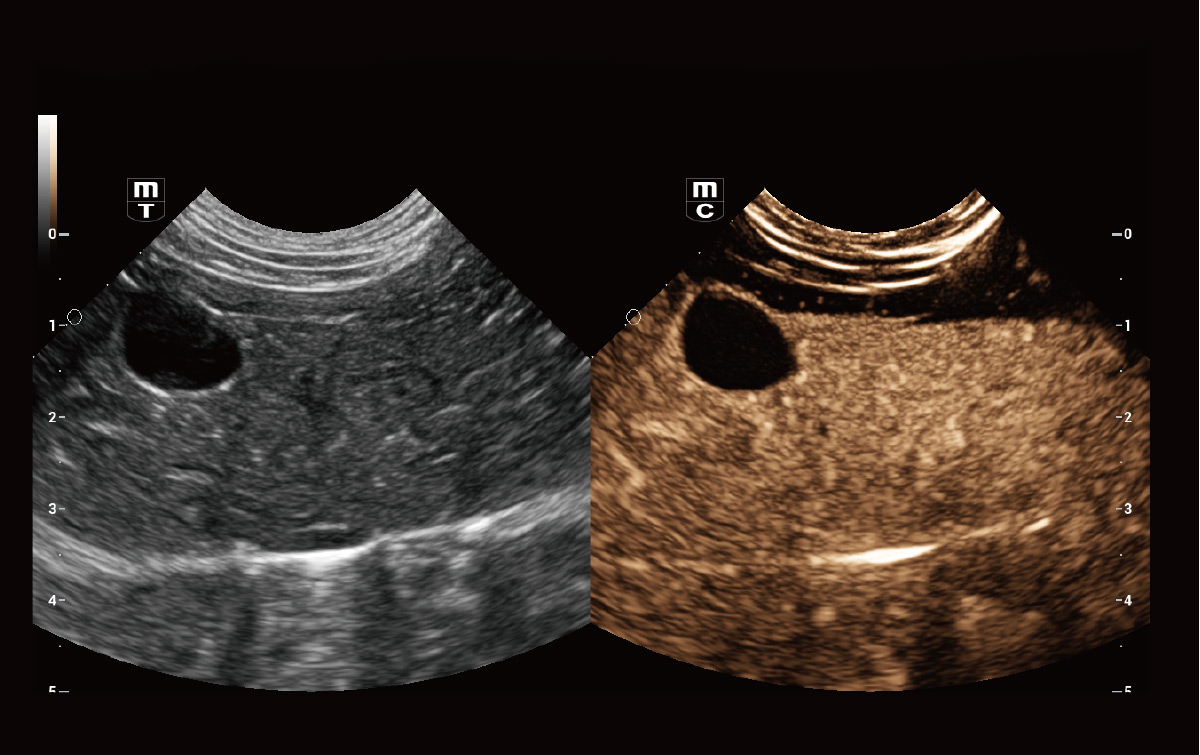

Diagnóstico de lesión focal con perfusión – UWN+ Imágenes de contraste

Detecta y utiliza señales fundamentales no lineales y de segundo armónico, generando imágenes significativamente mejoradas, lo que resulta en una mayor sensibilidad de señales menores y una mayor duración del agente con un IM más bajo.